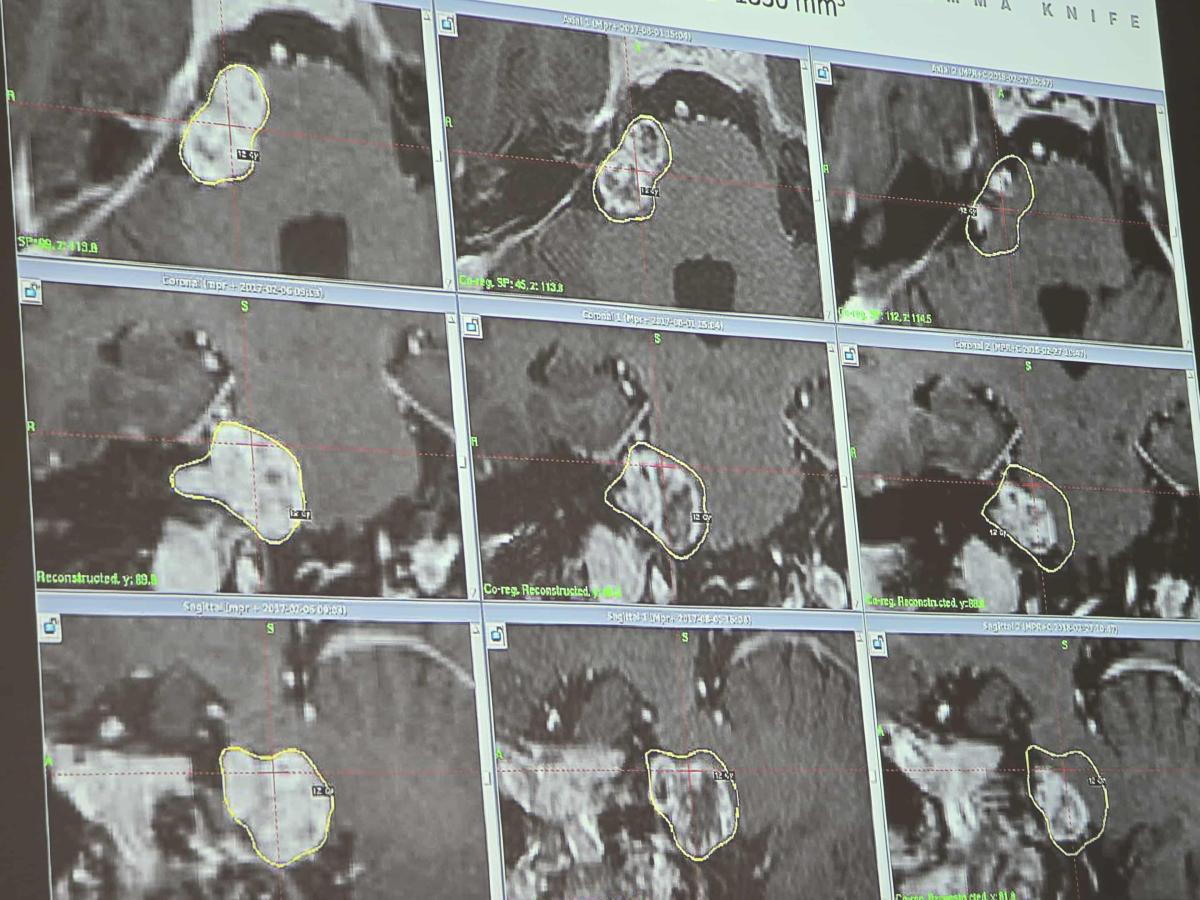

30 października 2025 toku uczniowie klasy 3A o profilu biologiczno-chemicznym mieli niezwykłą okazję wziąć udział w edukacyjnej wycieczce, która połączyła teorię z praktyką w najbardziej innowacyjnym wydaniu. W ramach rozszerzonego programu z biologii, uczniowie odwiedzili Centrum Radiochirurgii Gamma Knife Exira w Katowicach – placówkę, która jest pionierem w leczeniu guzów mózgu bez użycia tradycyjnego skalpela.

Jednym z głównych punktów wizyty było zapoznanie się z zasadą działania Gamma Knife – rewolucyjnej metody leczenia guzów mózgu, która wykorzystuje promieniowanie do precyzyjnego niszczenia nowotworów, eliminując konieczność tradycyjnego zabiegu chirurgicznego. Młodzież dowiedziała się, jak dokładnie działa ta przełomowa technologia, której precyzja w leczeniu jest porównywalna z umiejętnościami chirurga, ale bez użycia skalpela! To naprawdę wyjątkowe doświadczenie, które pokazało uczniom, jak zaawansowane technologie medyczne mogą zmieniać życie pacjentów na całym świecie.